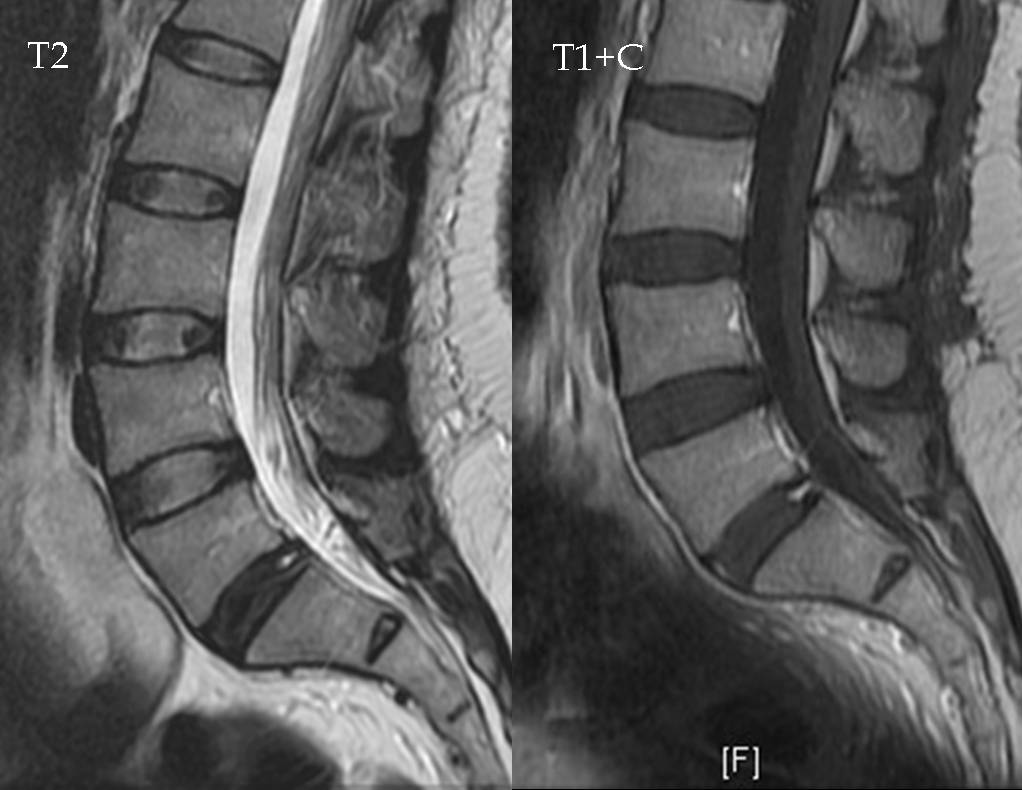

Для визуализации вышеописанных нозологических форм делают полипозиционное сканирование (в трех плоскостях). Чтобы не пропустить мелкие изменения рекомендуется выполнение срезов с шагом не менее чем 3-4 мм. Для выявления нозологических форм достаточно T2-взвешенного режима сканирования. Подход помогает выявить переломы, вывихи крестцово-подвздошного сочленения, генетические аномалии, кисты, корешковый синдром, выпячивание межпозвонковых дисков, воспаление, ущемление нервных волокон.

Зачем проводят томографию крестца с контрастом

Контрастирование проводится после нативного сканирования для обнаружения патологического очага, границы которого четко не установлены. После внутривенного введения препарата (гадовист, омнискан) оценивается накопление вещества вокруг исследуемого участка. Контрасты для магнитно-резонансной томографии не вызывают аллергии, быстро выводятся почками, не вступают в биохимические реакции. Ход ферментативных реакций гадолинийсодержащие препараты не изменяют.

Контрастирование копчика – что показывает:

- Нестабильность (смещение) отдельных позвонков, являющихся причиной компрессионного синдрома из-за ущемления нервных корешков;

- Подозрение на наличие участка высокой степени кровоснабжения при раковом новообразовании;

- При обнаружении онкологии – для определения размеров очага;

- Анализ любых объемных образований.